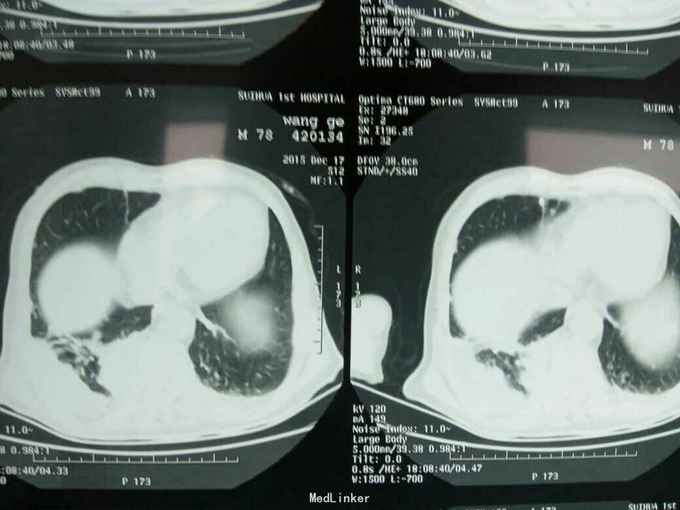

根据病史查体诊断:腰间盘突出症待确诊。应用消肿营养神经镇痛治疗。一天。查核磁共振示:腰椎多节段间盘突出伴椎管狭窄。第二腰椎骨破坏侵及椎板。部分突入椎管,脊髓受压。诊断:腰间盘突出伴椎管狭窄。第二腰椎转移癌,脊髓受压。经与家属沟通,查双肺CT:双肺下叶炎症。肺部纤维化。可见肿瘤阴影。肋骨及胸膜受累。胸椎部分骨破坏。最终诊断:双肺癌,胸椎,腰椎骨转移,脊髓受压。多节段腰椎间盘突出。病人至肿瘤科治疗。